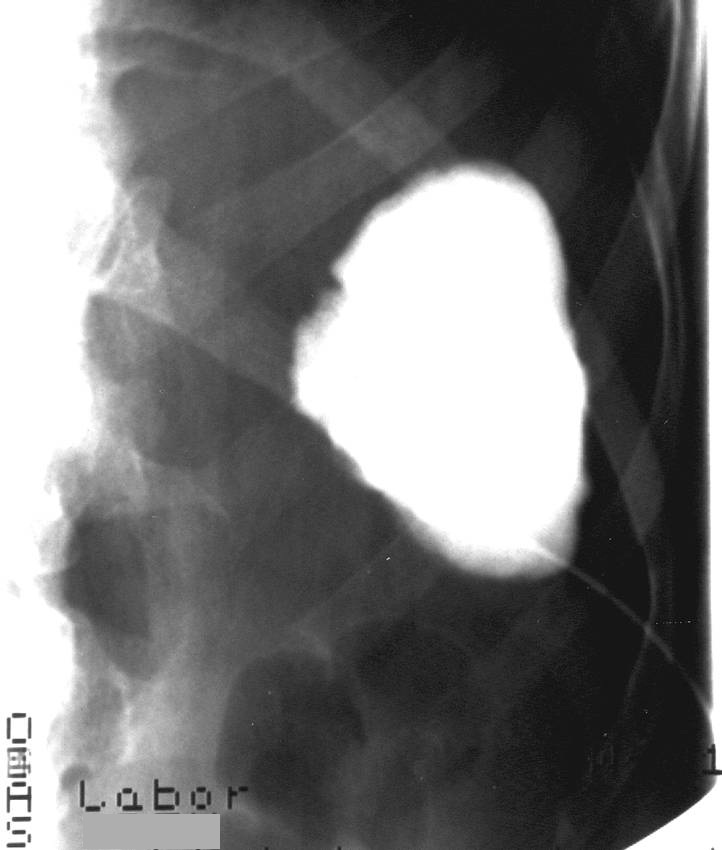

14.5.5. Cysts

The spleen cysts occur less frequently then the liver cysts, their morphological appearence is similar to that of the liver cysts (homogeneous, cystic content, sharp contour, thin wall, sometimes some thin septa). Most of them is detected only accidentally. It has a therapeutic consequence if its size increases resulting symptoms for the patient by the compression of the sorrounding tissues (Figure 47, 48).

A májcysták alkoholos sclerotisatiojához hasonlóan ezek a panaszt okozó lépcysták is kezelhetők (49. ábra), de nagyobb körültekintést igényelnek, mert a jelentősen vascularisaltabb lépparenchyma miatt a bevérzés esélye jóval nagyobb.

49. ábra Lépcysta rtg. felvétel, alkoholos sclerotisatio előtti kontrasztfeltöltés

Similarly to the alcoholic sclerotisation of the liver cysts, these symptomatic splenic cysts can be also treated (Figure 49), but more circumspection is needed, since the chance of hemorrhage is higher because of the notably vascularisated splenic parenchyma.